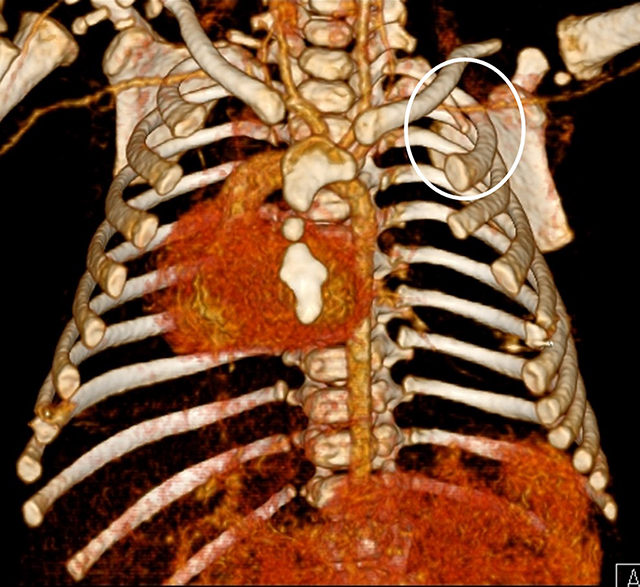

Figure 4

3D reconstruction of the chest CT-scan shows a dysplastic left sternal half and a dextroposition of the heart. There is a hypoplastic first rib on the left side (circle).